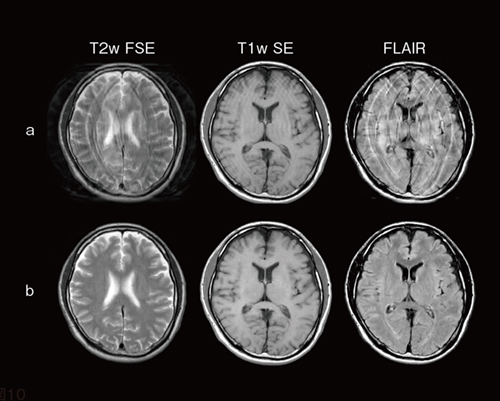

図2 体動アーチファクト画像(a)とStillShotによる再構成画像(b)

体動アーチファクトが発生した画像(a)を撮像後,StillShotで画像再構成をすることにより,体動アーチファクトを低減した画像(b)を生成することができる。